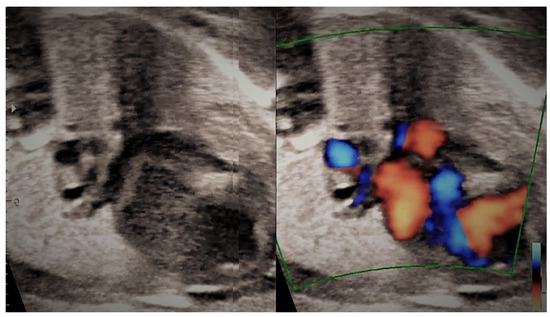

4.3. Case 3